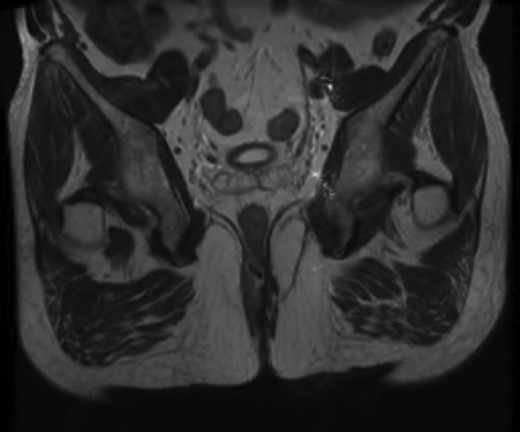

Given the high likelihood of significant vascular disease, a computed tomography (CT) angiogram was done (Fig. 1). Bilateral internal iliac artery stenosis was noted with complete occlusion of the inferior mesenteric artery and right internal iliac artery. A positron emission tomography (PET) scan showed only localized disease (Fig. 2). Magnetic resonance imaging (MRI) of his pelvis was significant for a large posterior abscess cavity with soft tissue at the margins with a cavity tracking superiorly along the posterior rectal plane (Fig. 3). The internal sphincter was noted to be necrotic on the last examination (Fig. 4) with a horseshoe cavity and a 10-cm tract running up the posterior aspect of the rectum. Multiple biopsies were taken from the anal margin, abscess cavity and peri-anal tissue, and the histology was consistent with diffuse large B-cell lymphoma. There were sheets of large atypical lymphocytes with extensive areas of necrosis. The tumour cells showed strong and diffuse immunohistochemical reactivity for CD20 (Fig. 5), indicating B-cell differentiation. The Ki67 proliferation index was very high (>90%) (Fig. 6) and there was positive in situ hybridisation (ISH) for Epstein-Barr virus (EBV) (Fig. 7). Fluorescence in situ hybridisation (FISH) was performed using a MYC dual colour break apart probe (8q24), and no rearrangement of the MYC gene region was detected. The combined morphological and FISH features were not considered to be those of Burkitt lymphoma.

Necrotic internal sphincter and abscess cavity at the posterior aspect of the rectum.